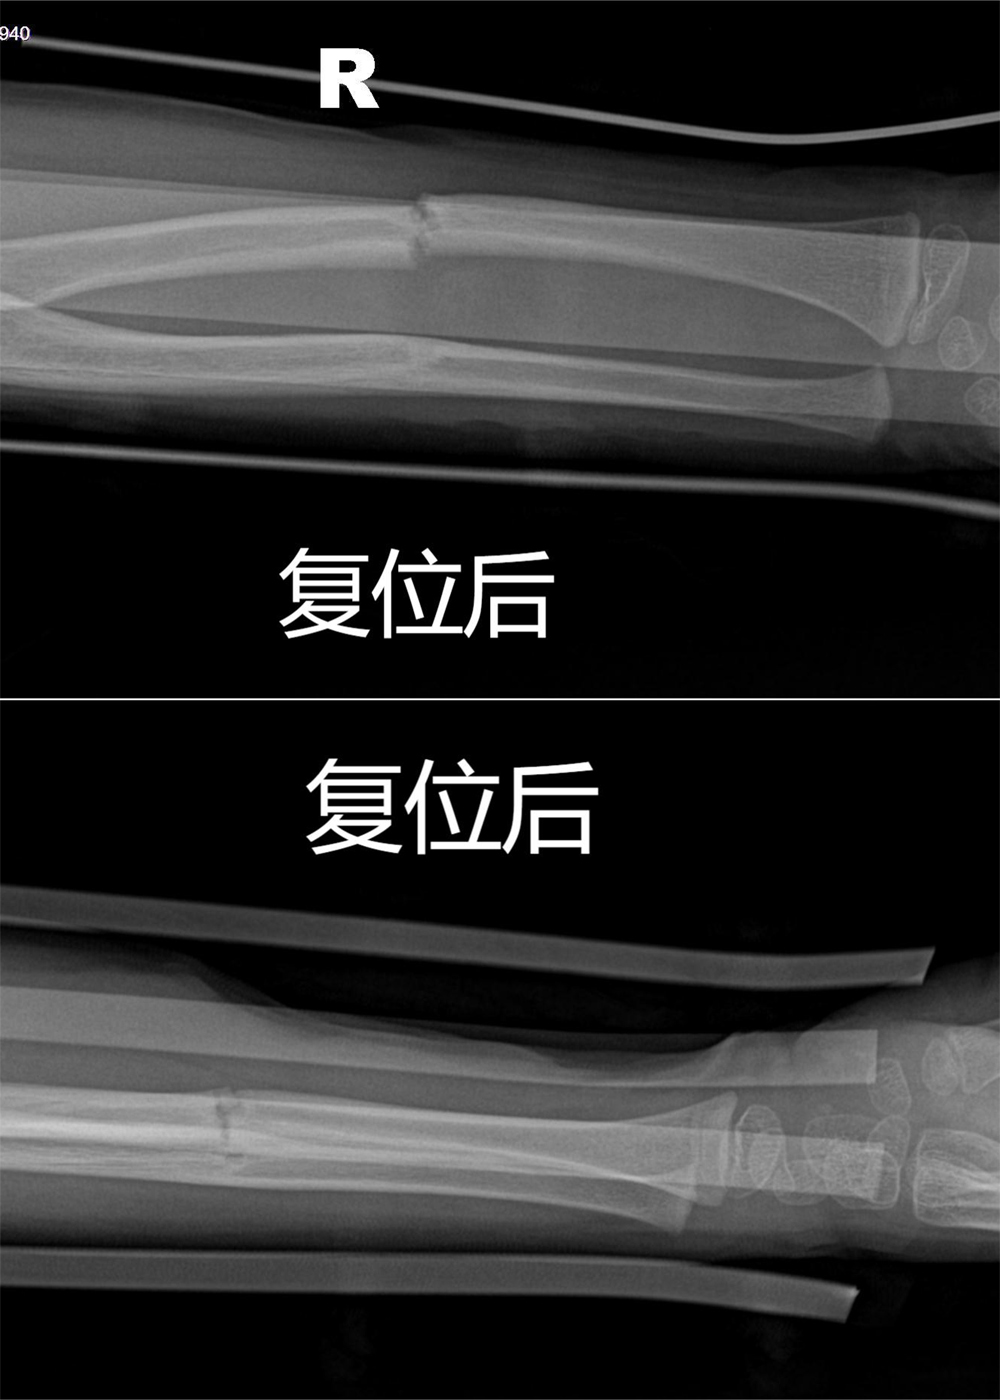

行手法复位后对位对线理想,小夹板固定,予以接骨膏药,消肿止痛效果明显,患儿痛苦小。

复位后.jpg